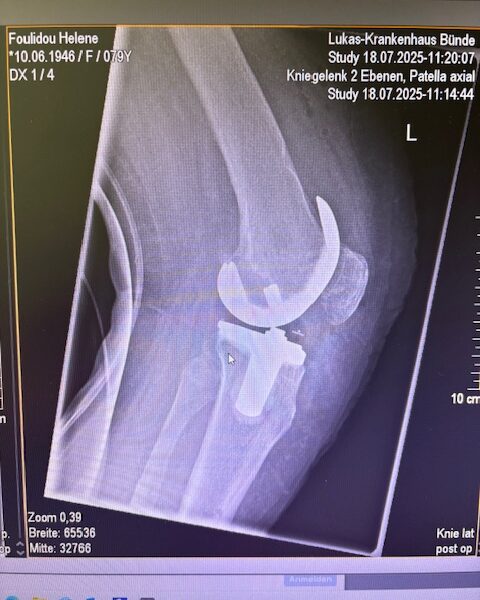

Τα εμφυτεύματα που χρησιμοποιήθηκαν στο γόνατο της ασθενούς είναι της Aesculap: E-Motion Pro, μηριαίο μέγεθος 4, κνημιαίο μέγεθος 4, με ενθέμα (inlay) 10mm.

Ήδη από τις πρώτες εβδομάδες, περπατούσε χωρίς πόνο, με βελτιωμένο εύρος κίνησης.   Η παθητική κίνηση κατα την έξοδο της ασθενούς από την κλινική ήταν E/F : 0-0-120 Επίσης πλήρη σταθερότητα του γόνατος σε κάμψη και έκταση.